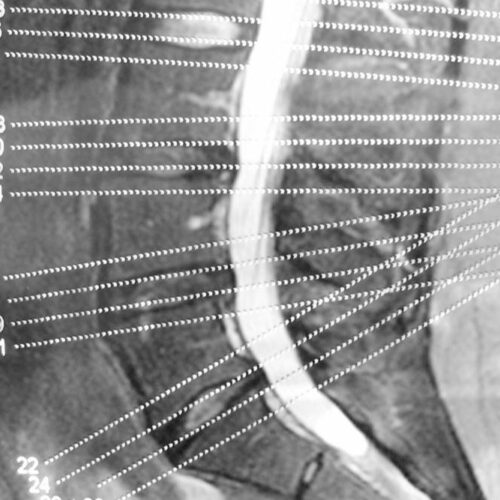

When you mention the term degenerative disease, it refers to the gradual deterioration of the body tissues or cells over the years due to the natural aging process. As we age, our spine starts giving in to the stress of providing flexibility and support to our back. The components of the spine start deteriorating slowly, and you will experience back pain and stiffness in the spine.